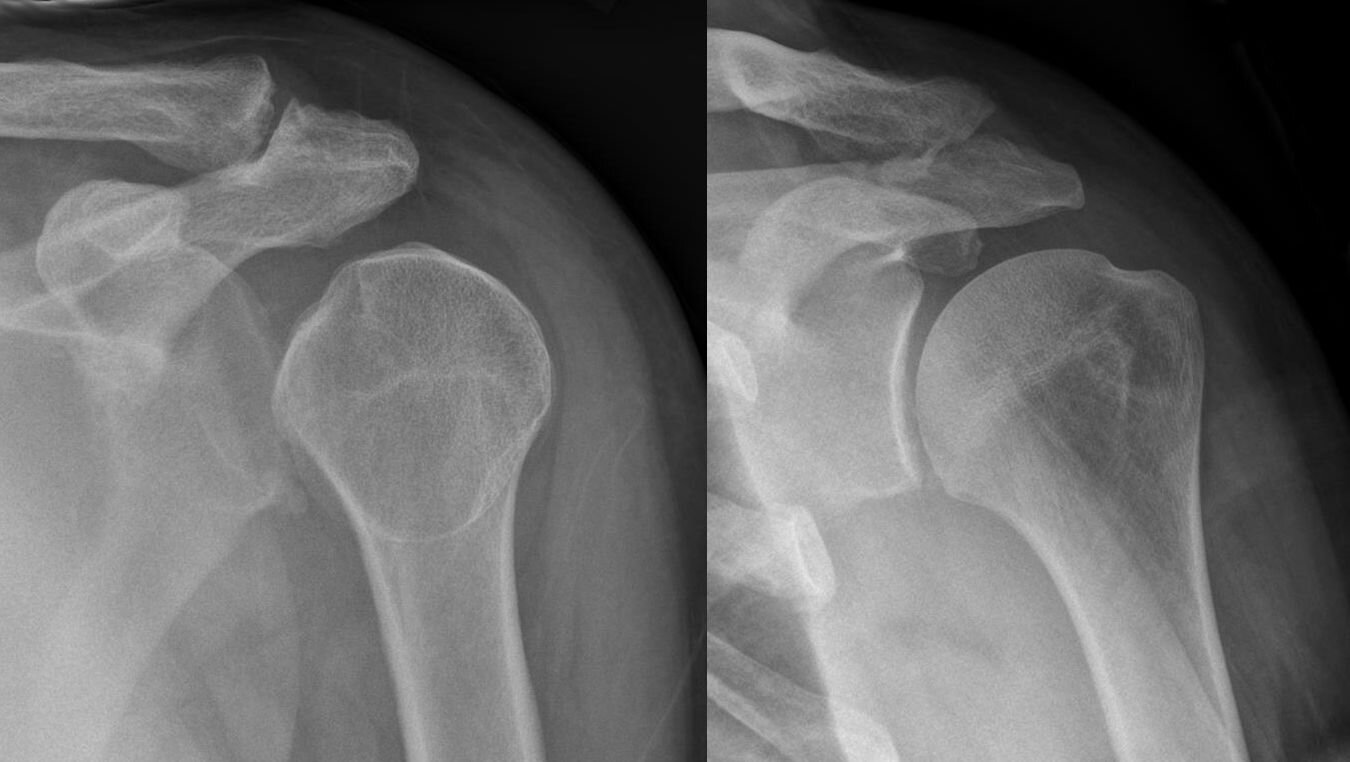

Na podstawie fotografii wyjaśnij, na czym polega zwichnięcie stawu. (Uzupełnij).

Zdjęcie rentgenowskie: zwichnięty staw barkowy (po lewej) oraz zdrowy (po prawej).

Źródło: Hellerhoff, Wikimedia Commons, licencja: CC BY-SA 3.0.

Zwróć uwagę na układ kości ramiennej na zdjęciu rentgenowskim.

Zwichnięcie stawu ramiennego prowadzi do utraty łączności kości, które są połączone tym stawem. Zwichnięciu towarzyszy naciągnięcie bądź rozerwanie torebki stawowej, otaczającej staw.